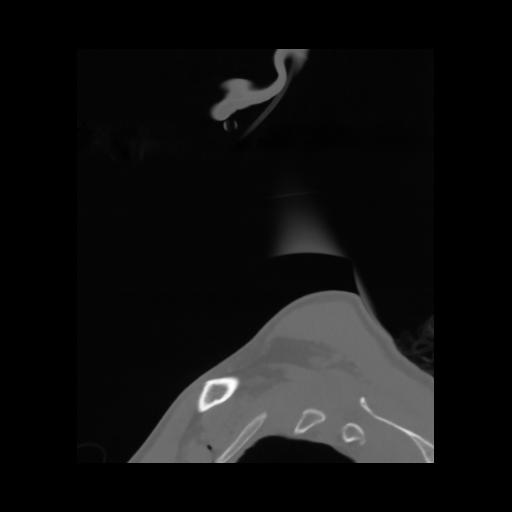

14 P.BLANDAS,,Sagittal,2.000,P.BLANDAS,Sagittal,